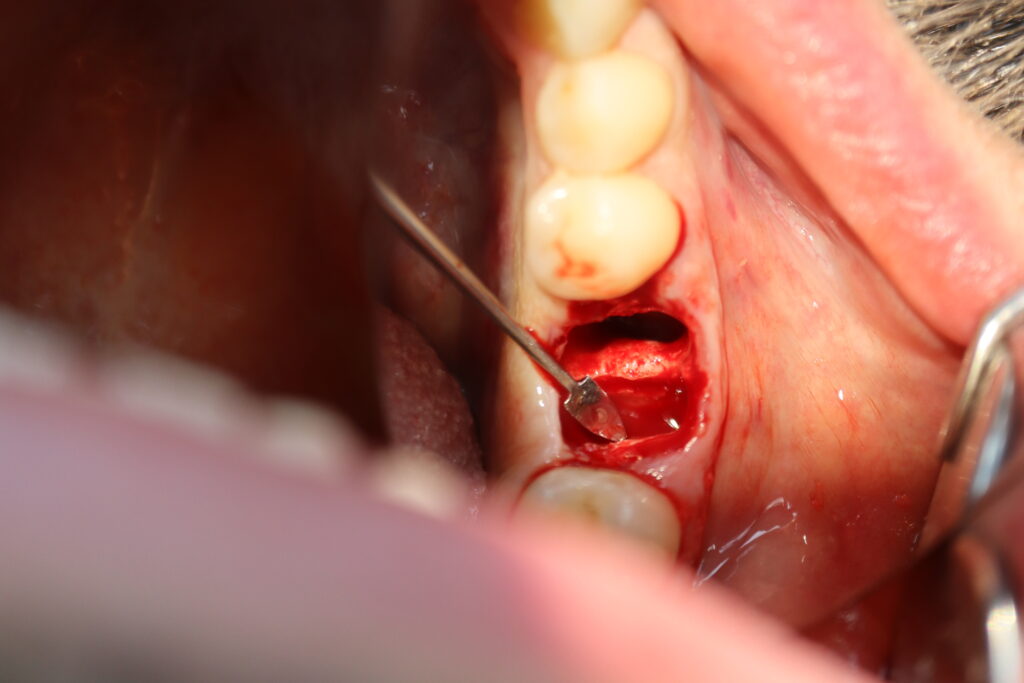

Процесс работы

Что было сделано:

За одно посещение был удален зуб 3.6 и установлен имплантат Megagen AnyOne, установлен формирователь десневой манжетки.

процедура имплантации

Это фото может содержать тяжелый для восприятия контент